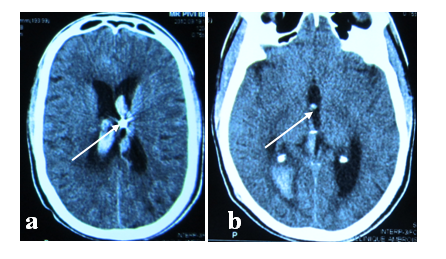

Figure 2 Axial, Frontal and Sagittal CT scan showing the penetration of the foreign body near the midline and deep into the right frontal region with the tip in the 3rd ventricle floor (white arrows).

CT scan of the head showed the nail had penetrated 1 cm lateral to the midline and 3.5 cm deep into the right frontal region. Surgery was delayed due to the absence of a qualified anesthesia team in the hospital at that time. On the following days, the patient presented a progressive decline in neurologic status with a GCS of 10/15, left hemiplegia, fever, and neck rigidity. Two weeks after the initial evaluation, circumferential craniotomy was performed and the nail was removed along with a bone flap. We observed an abundant purulent fluid coming out of the narrow cavity created by the nail in the brain parenchyma. The cavity was drained. Necrotic brain tissue and bone fragments were also removed followed by rigorous hemostasis and generous irrigation. There was no vascular injury. The dura was closed, and a small duroplasty was made using the pericranium. The wound was closed after debridement of the track. The patient had an uneventful post-operative course and his neurological impairments recovered completely within 10 days. He received intravenous Ceftriaxone and Flagyl for 3 weeks. He was then discharged with recommendations to take Gardenal (Phenobarbital) for 6 months. He was advised to return for monthly follow-up. There has been no report of seizure at the last follow up visit.

Penetrating intracranial injuries are uncommon in the civilian medical environment. The most common types of such injuries include occupational incidents, and criminal assaults. A 34-year-old prisoner with an intracranial injury produced by a nail is presented. Imaging studies showed that the nail had penetrated 1 cm lateral to the midline and 4.5 cm deep into the right frontal region with the tip in the third ventricle. Despite a 2-week delay in the treatment, the patient experienced a remarkably good recovery in a 2 years follow up.